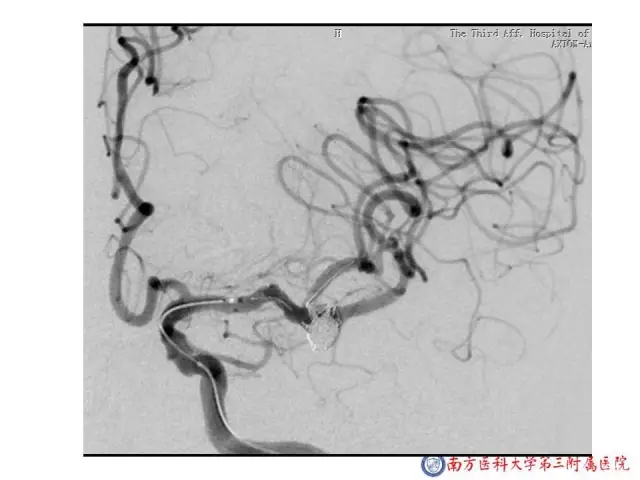

今天为大家分享的是“强生医疗CNV-神经介入专栏”第二十五期,由南方医科大学第三附属医院神经外科主任黄理金教授带来的“Enterprise支架辅助栓塞动脉瘤的优势”精彩讲课视频及PPT,欢迎观看。文章仅代表作者个人观点,如有不同见解,欢迎同道斧正!